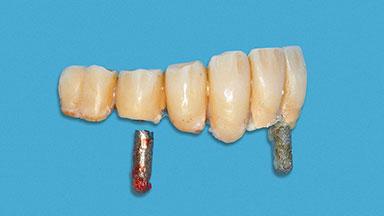

A 93-year-old female patient presented in September 2010 with an enlarged swelling on the lingual side of her lower incisors. At the time, she was essentially healthy, except for reduced vision due to bilateral age-related macular degeneration. She had been a heavy smoker (about 30 cigarettes a day) for the past 20 years after becoming a widow. The patient lived at home by herself, with full-time domestic support. An extraoral examination revealed nothing adverse. Intraoral plaque control was anything but ideal, and a soft-tissue tumescence was visible around the lingual aspect of 41–42. Because the nature of the lesion was not clear, a biopsy was carried out that revealed the inflammatory nature of the lesion. The panoramic radiograph showed six irregularly distributed mandibular implants supporting a full-arch prosthesis, with various degrees of interproximal peri-implant resorption. The periapical radiograph revealed interproximal bone resorption mesially and distally to implant 41.

Prosthesis Type FDP